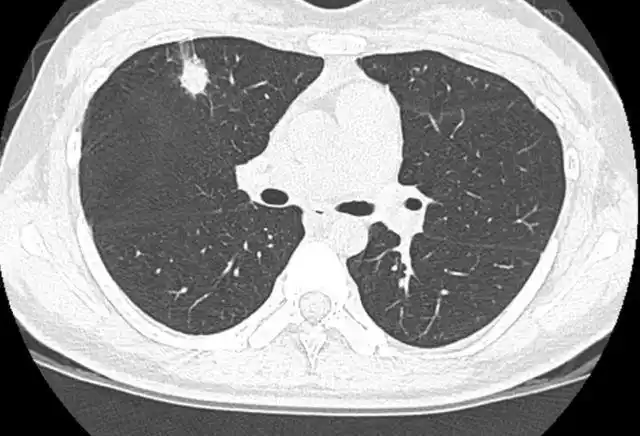

刘懿博士说肺癌二五九〇切之前知道俩肺结节是良性但不是一种病

刘懿博士说肺癌(二亖一六)9毫米肺结节形态不规则,一定是肺癌么?

体检发现肺结节,一定是肺癌吗?

肺结节如何分辨,我手把手教你!